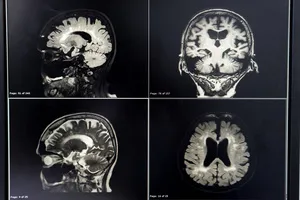

뇌경색 후유증은 뇌 손상 부위와 정도에 따라 다양하게 나타나며, 개인마다 경험하는 증상과 정도가 다를 수 있습니다.

1. 마비

팔다리의 힘이 약해지거나 움직이지 못하는 상태입니다. 손상된 뇌 부위에 따라 한쪽 팔다리만 마비되거나 양쪽 모두 마비될 수 있습니다.

2. 불안정한 자세

균형 감각이 떨어져 자주 넘어지거나 비틀거리는 증상이 나타날 수 있습니다. 이는 뇌에 특정 부위, 특히 소뇌나 뇌간의 손상으로 인해 발생할 수 있습니다.

3. 언어 및 인지 기능 장애

말을 유창하게 하거나 복잡한 문장을 만들기 어려워지며, 다른 사람의 말을 이해하기 어려워집니다. 읽기 및 쓰기 장애, 기억력 감퇴, 집중력 저하, 판단력 저하 등이 나타날 수 있습니다.